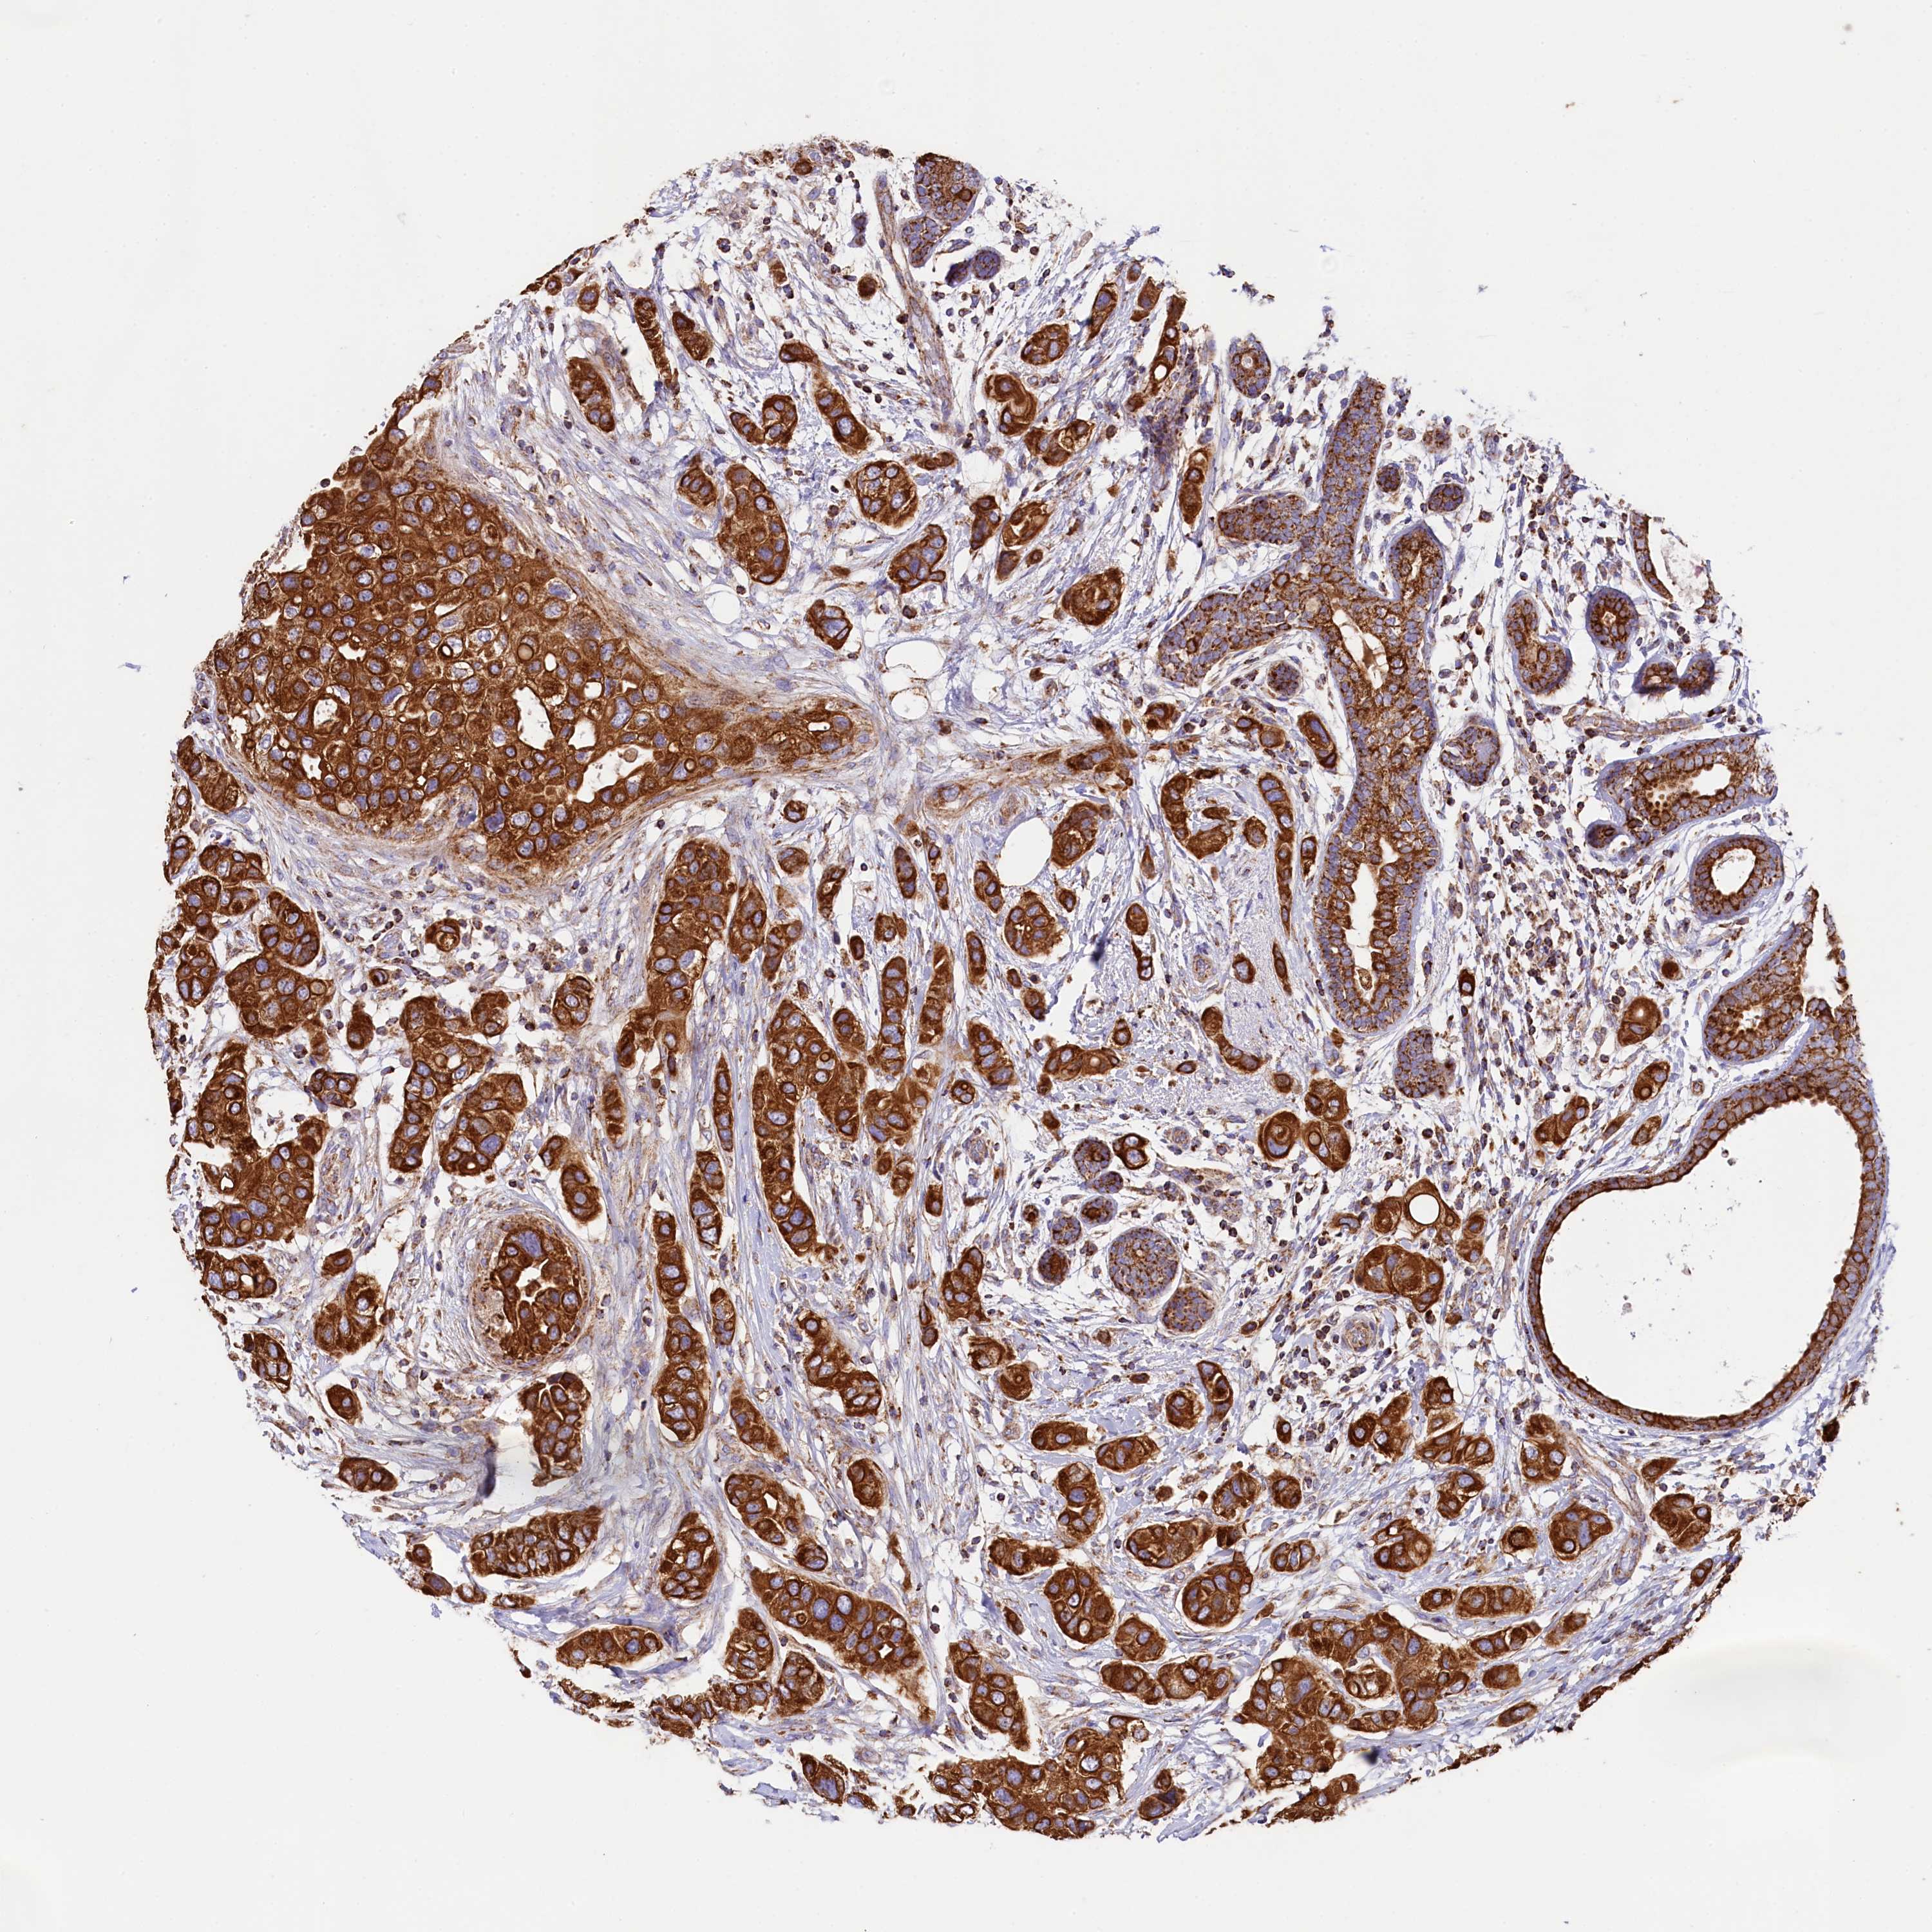

CANCER BREAST CANCER Show tissue menu

BRCA TCGA BRCA VALIDATION PROTEIN EXPRESSION